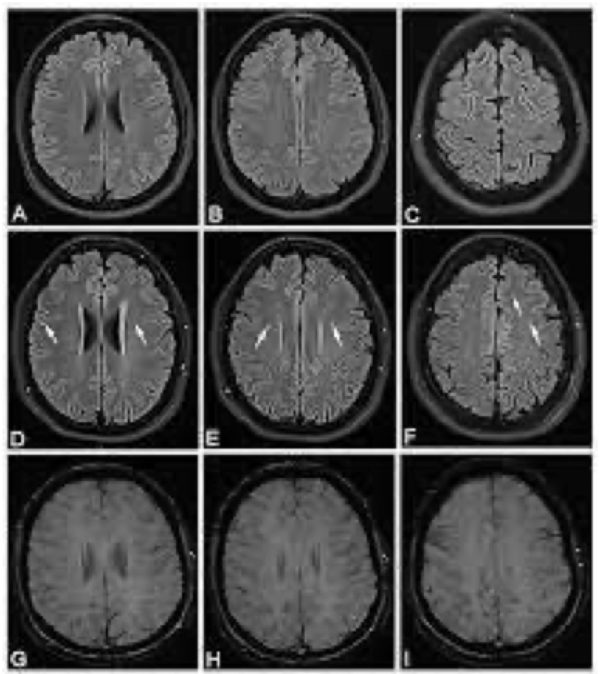

왼쪽 MRI 사진은 마치 부검한 것처럼 뇌를 잘라놓은 듯이 보입니다. 사진을 보시면 회백질과 백질 그리고 가운데 나비 모양으로 비어 있는 뇌실이 검은색으로 나타난 것을 찾을 수 있습니다. 이는 뇌실이 물로 차 있고, 물 분자는 확산이 잘되면 검은색으로 보이기 때문입니다.